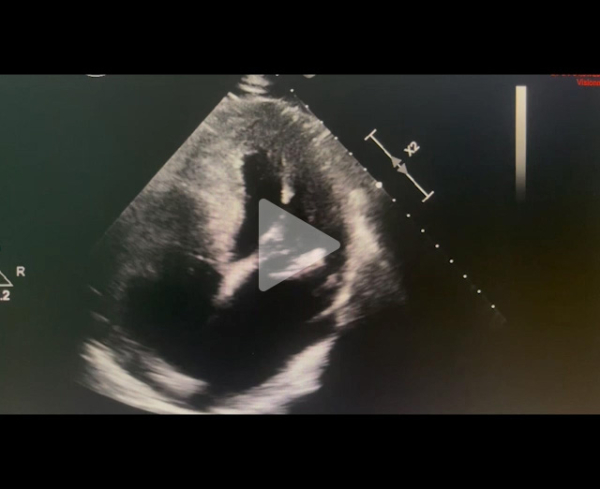

Echographie cardiaque transthoracique : PSGGA

Vidéo 1

Vidéo 2

Vidéo 3